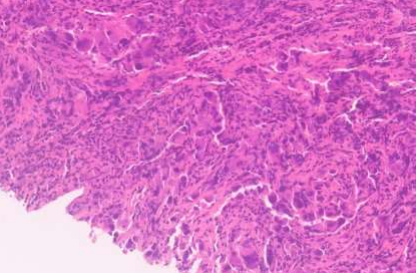

Based on the CT findings, a lung primary was suspected. A lung core tissue biopsy was taken on the 28th of March. It revealed non-small cell lung cancer; most likely a poorly differentiated SQUAMOUS cell carcinoma (SCC). The background stroma was desmoplastic with a near absence of associated chronic inflammation, there was no tumour infiltrating lymphocytes (TILs).

Fig. 3: lung biopsy

Fig.4: lung biopsy

It was positive for p40, p63, D2-40 (80%), Calretinin (40%), CK, CK7 and Synaptophysin.

It was negative for TTF1, S100, Melan A, WT1, INSM1, CD56, PSA, NKX3.1, AFP and CD30.  The diffuse strong positivity for p40 made it unlikely to be an adenocarcinoma, since p40 is present in <5% of lung adenocarcinomas and only show a focal expression, if present.

PD-L1 IHC 22C3 pharmDx result: Tumor Proportion Score (TPS) 0%.

Oncomine Comprehensive Assay (DNA) showed: KRAS: c.34G>T, p.(G12C).

Oncomine Comprehensive Assay (RNA): NO REARRANGEMENT DETECTED.

Microsatellite Instability Status: Stable (MS-S).